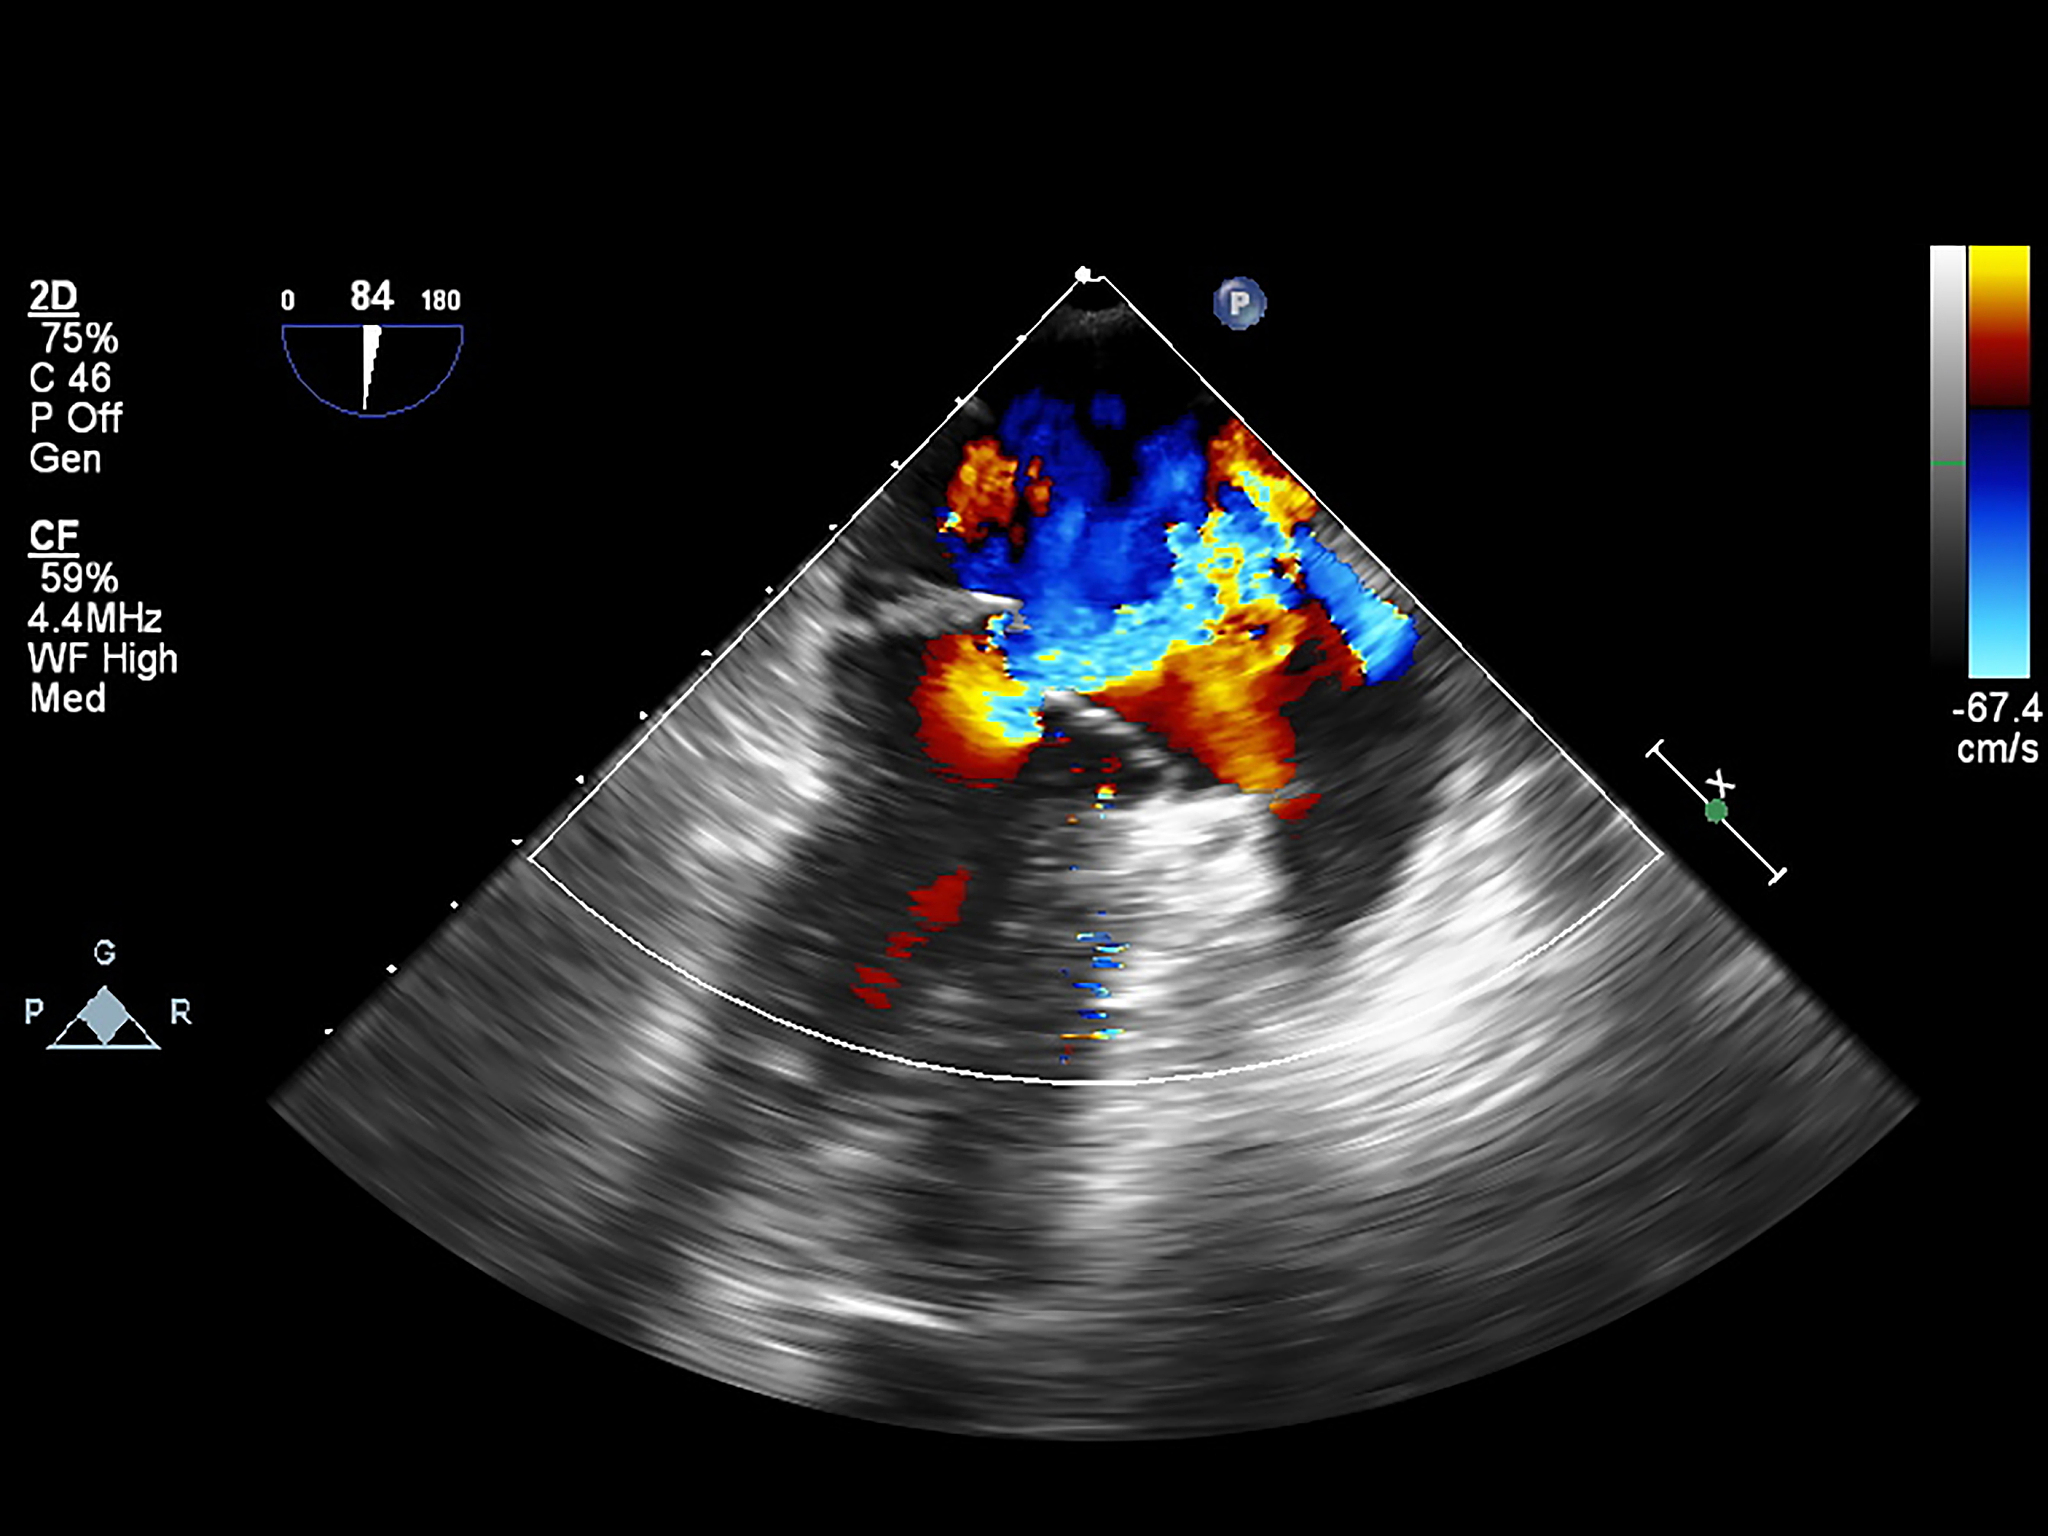

血管内超声诊断导管头端的显影性是指导管头部分在超声图像中的清晰程度和亮度。它的意义在于:

1. 确定导管头位置:导管头清晰亮度越高,表示导管头部分越容易被识别和确定位置,有助于医生准确放置导管。

2. 发现导管头异常:如果导管头部分呈现不规则形状或显影性差,可能是导管头部分发生了异常,需要进一步观察和处理。

3. 判断导管位置和通畅性:导管头显影性好,可以观察导管是否位于正确位置,并且是否通畅,有助于及时发现导管位置异常或者阻塞。

综上所述,血管内超声诊断导管头端的显影性对于导管的放置、观察和处理都具有重要意义。